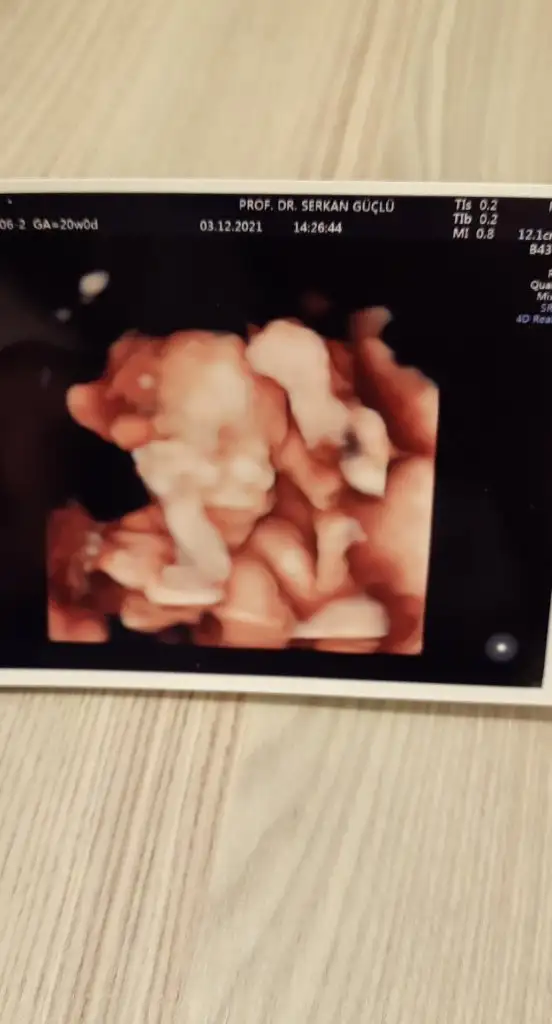

Şükrediyorum ki tekrar ettim detaylıyı ve bu kadar ilgilenildi bugün benimle. 3 kere denedi radyolog sağolsun ara vere vere.